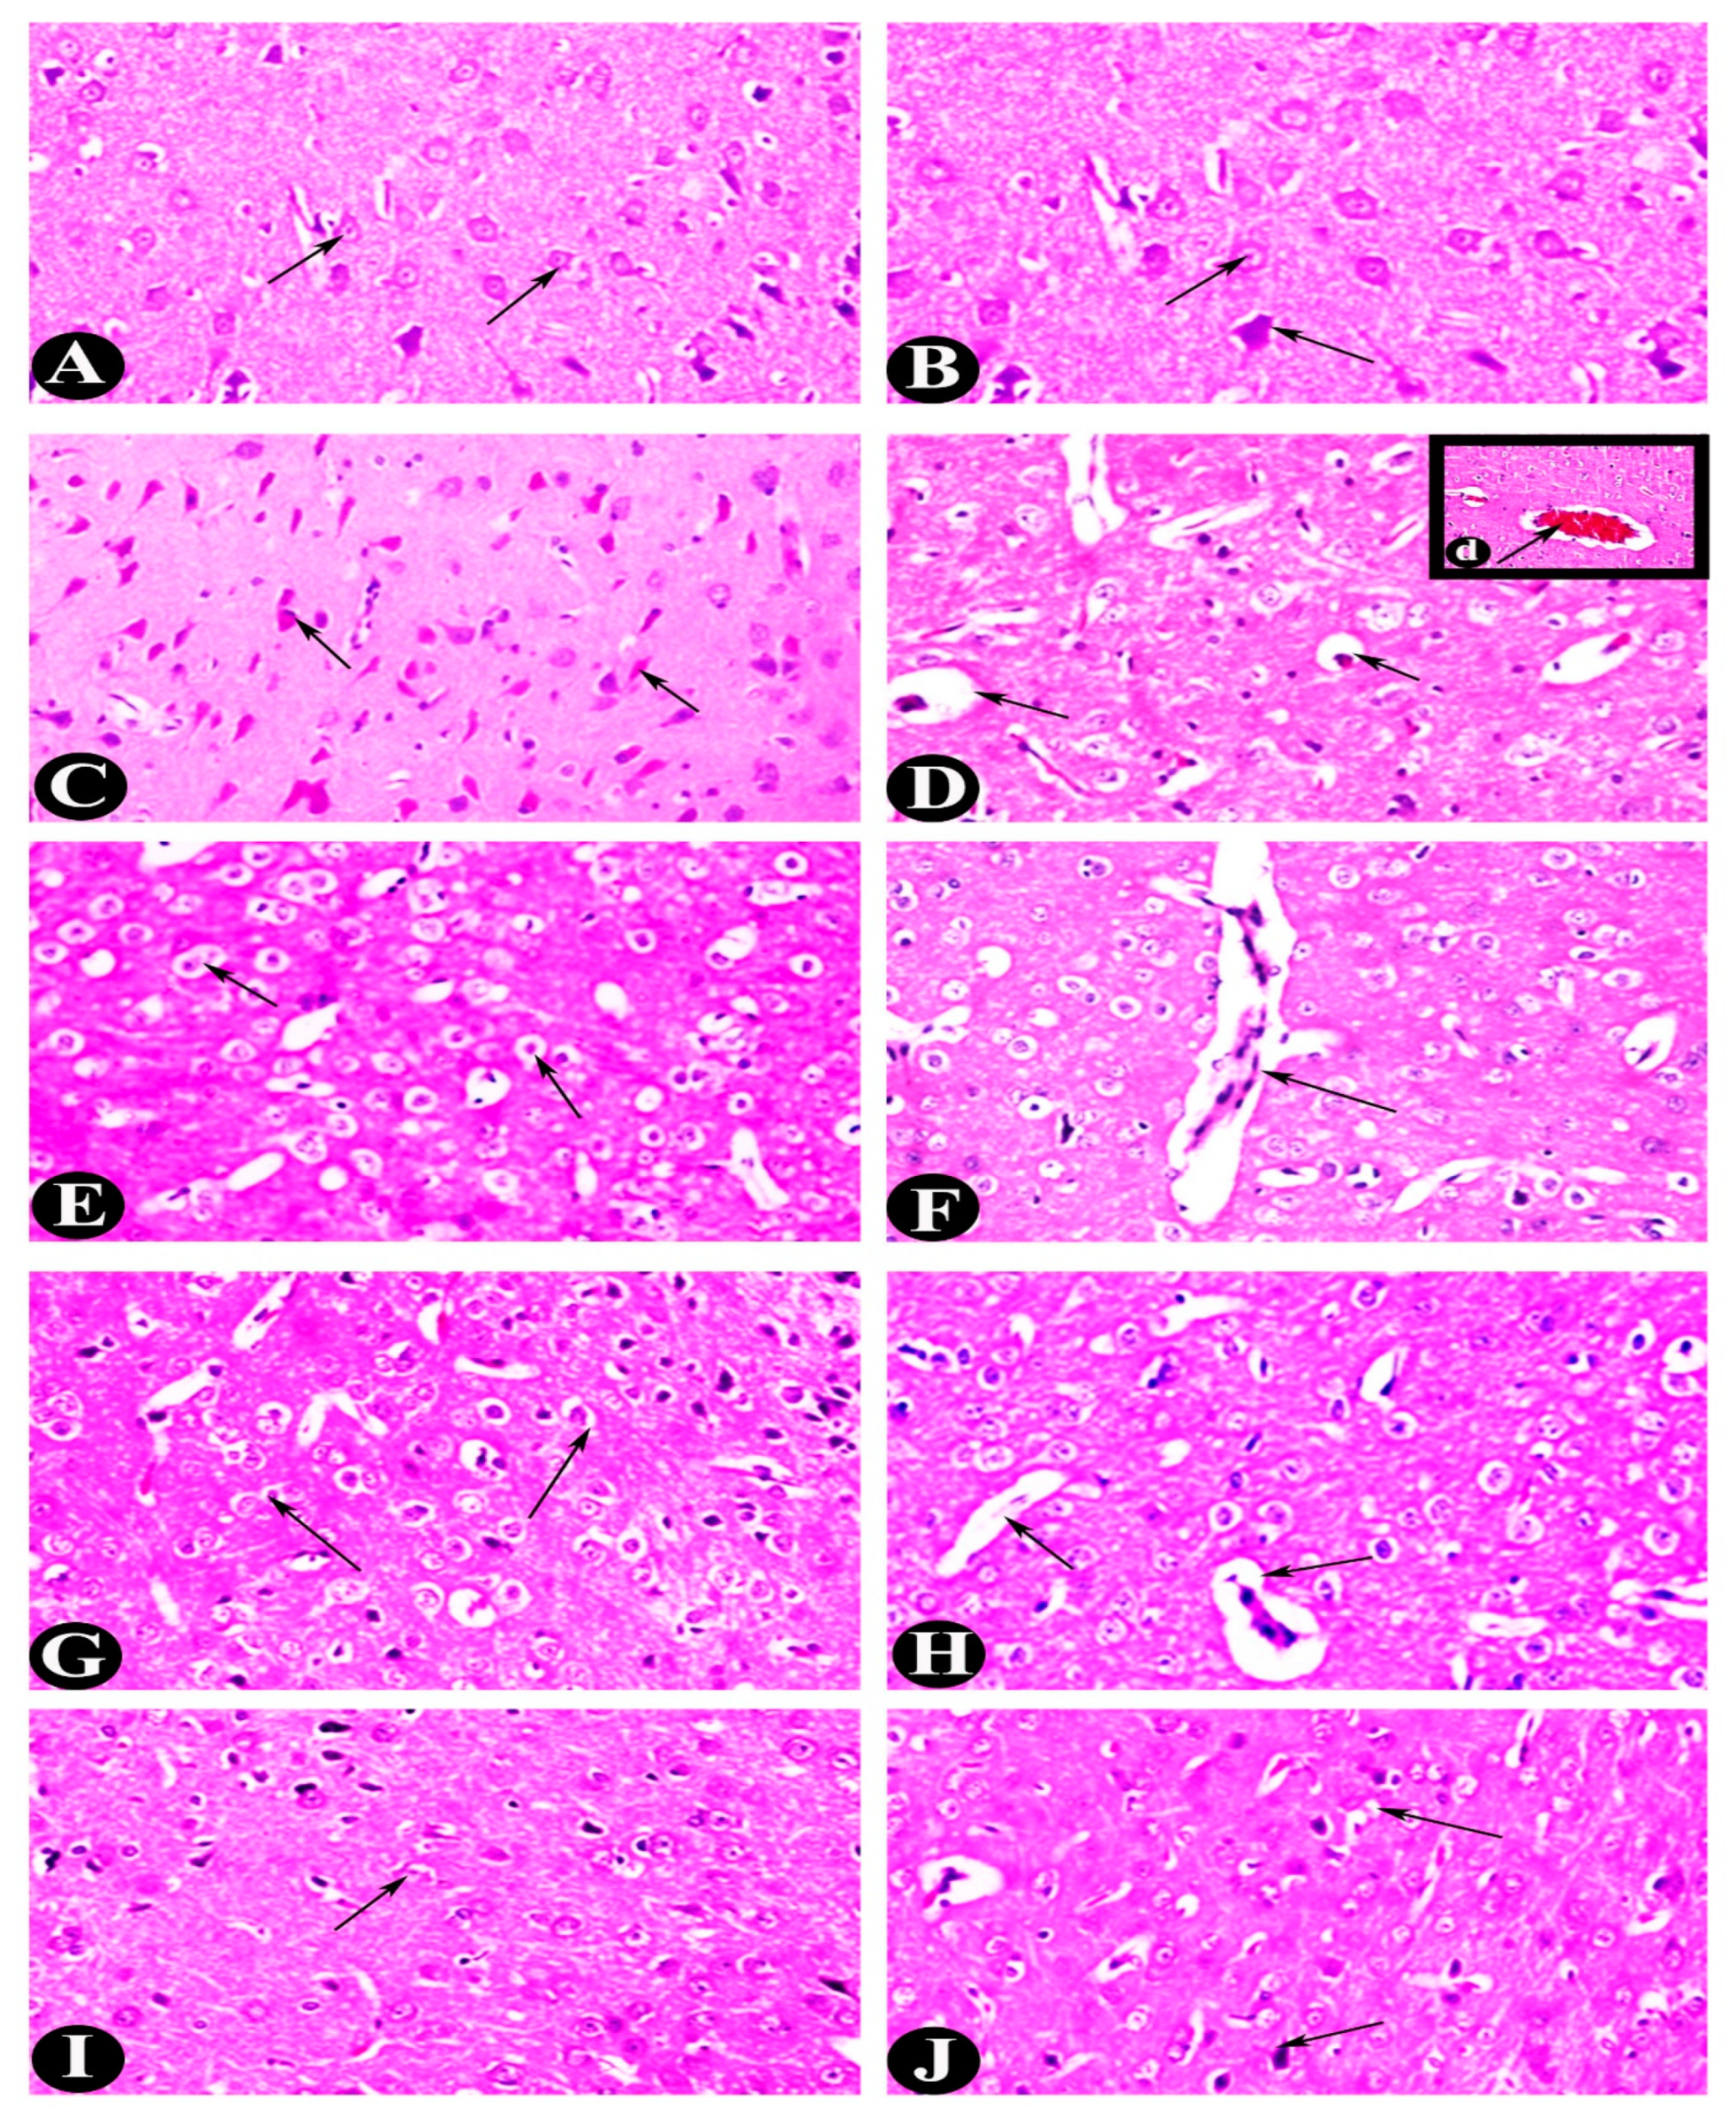

2.3. Histopathological Alterations (H&E)

| Groups | Average Cerebral Neurons (cells/mm2) | Degenerative Neurons (cells/mm2) | Average Glial (cells/m2) | Cerebellum Thickness (mm) | Number of Blood Vessels | Hippocampus Degenerative Neurons (cells/mm2) |

|---|---|---|---|---|---|---|

| Control | 25.500 ± 2.739 c | 10.313 ± 1.559 a | 42.333 ± 2.582 c | 48,948.180 ± 1997.897 c | 7.167 ± 1.722 c | 4.688 ± 0.552 a |

| EP | 13.333 ± 2.251 a | 19.254 ± 2.451 c | 29.500 ± 4.764 a | 38,617.459 ± 1783.434 a | 2.000 ± 1.095 a | 12.604 ± 1.074 b |

| EP-VPA | 20.333 ± 1.633 b | 14.844 ± 3.575 b | 40.167 ± 1.941 bc | 44,809.778 ± 1196.650 b | 3.333 ± 1.366 ab | 11.083 ± 1.139 b |

| EP-LO | 21.167 ± 2.137 b | 10.067 ± 0.467 a | 36.167 ± 2.229 b | 49,689.334 ± 2101.564 c | 4.500 ± 1.049 b | 6.417 ± 1.400 a |

| EP-LX | 22.167 ± 3.189 bc | 10.067 ± 0.467 a | 36.333 ± 2.805 b | 49,856.001 ± 3211.469 c | 5.000 ± 1.414 b | 6.417 ± 1.400 a |

| F value | 19.925 | 23.175 | 15.633 | 29.683 | 12.254 | 52.127 |

| p < | 0.0000 | 0.0000 | 0.0000 | 0.0000 | 0.0000 | 0.0000 |